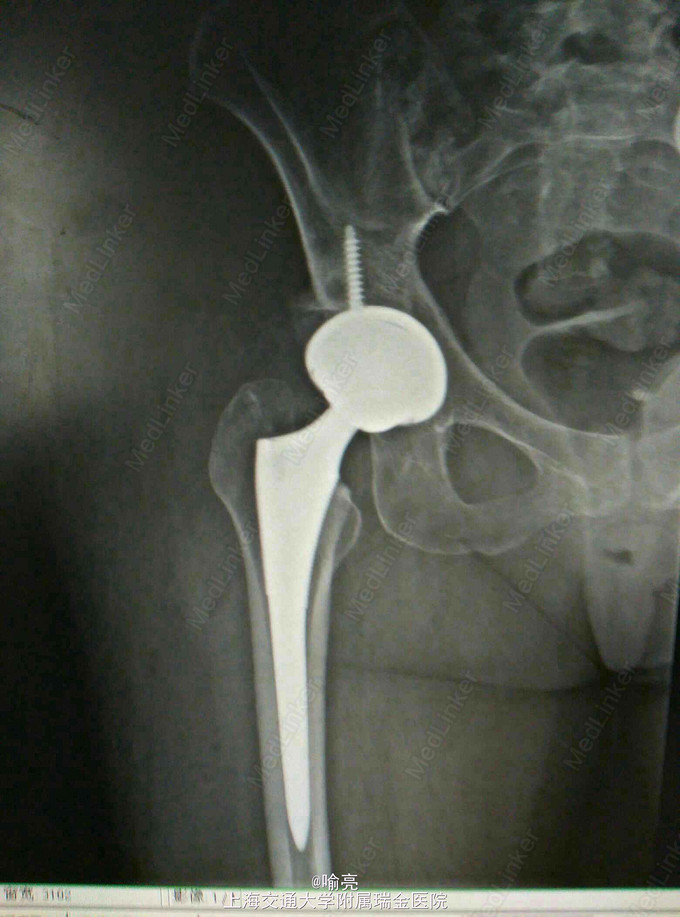

诊断:DDH继发髋关节退变 治疗:右侧THA

3月后复查患者右侧髋关节疼痛消失,活动度可。预约拟行左侧髋关节置换术。 由于DDH髋关节覆盖不足,只要髋关节前后壁是完整的,髋臼杯仍能固定稳定。髋臼螺钉仅能增加早期的稳定性。长期稳定性要靠臼杯和髋臼的压配。